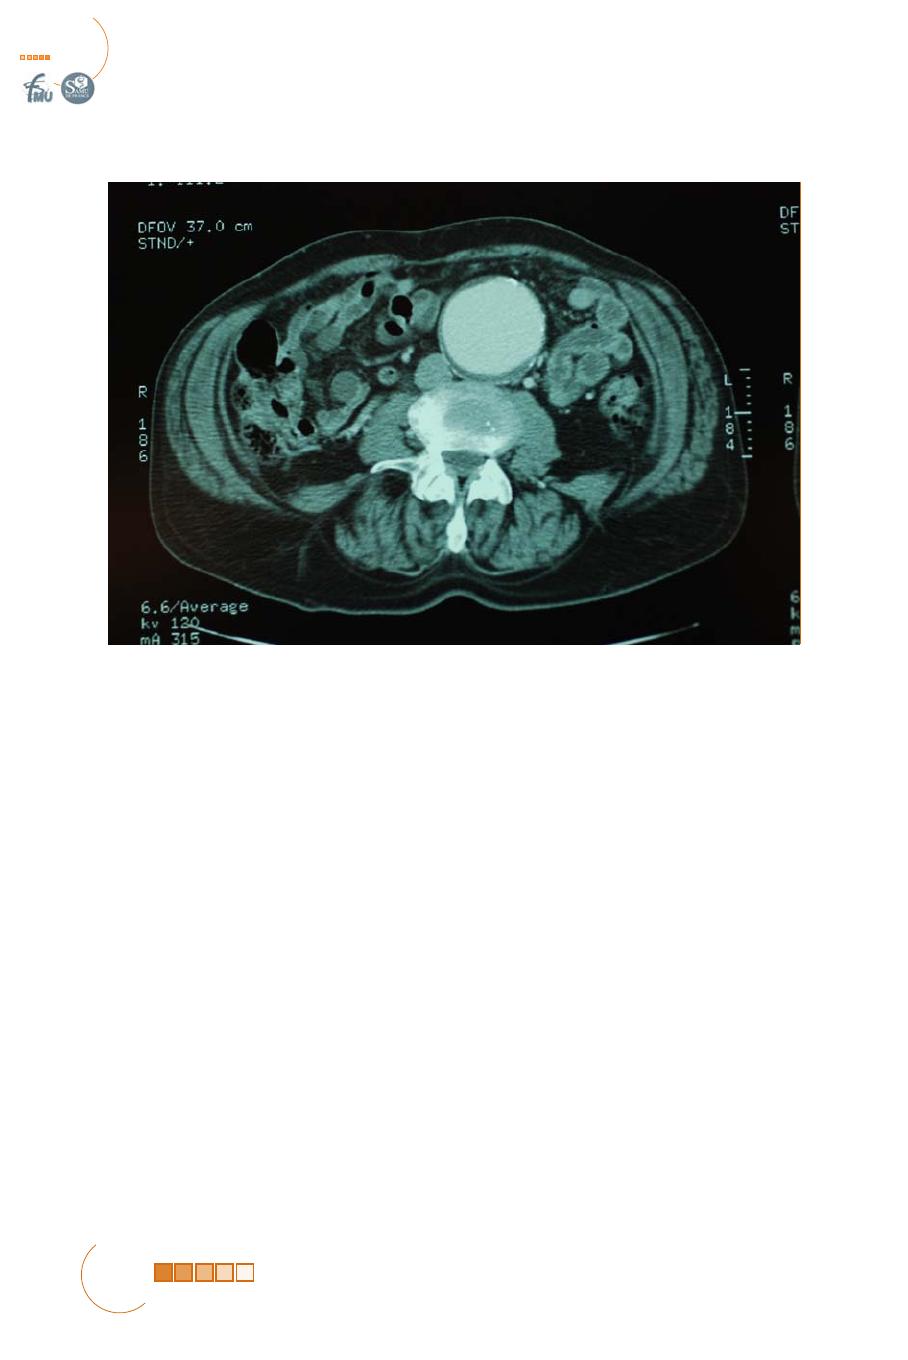

ANÉVRYSME AORTIQUE ABDOMINAL FISSURÉ OU ROMPU

Les autres symptômes pouvant être observés dans les AAA instables sont

essentiellement liés à la compression des organes de voisinage. La compression

peut intéresser le duodénum (signes d’occlusion digestive haute), les troncs

veineux iliaques (œdème des membres inférieurs, thrombose veineuse profonde)

les nerfs du plexus lombaire (sciatalgies, cruralgies), les corps vertébraux qui